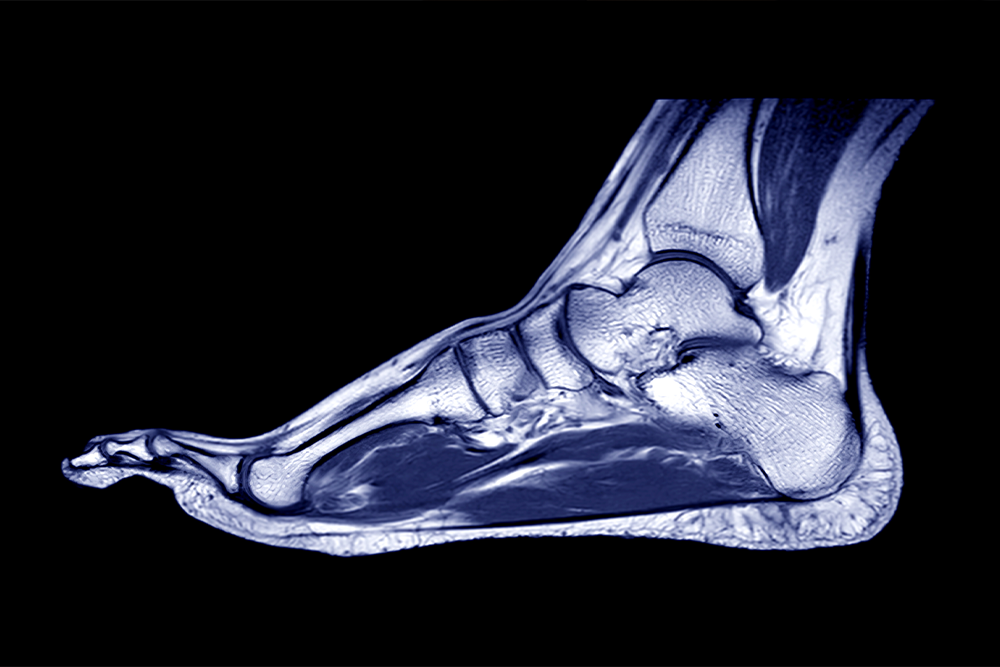

Non-Invasive MRI Scans for Foot and Ankle Conditions

Magnetic Resonance Imaging (MRI) is a powerful, non-invasive diagnostic tool used to capture detailed images of the bones, joints, and soft tissues in your feet and ankles. Unlike X-rays or CAT scans, MRI uses magnetic fields and radio waves instead of radiation, making it a safe and effective choice for patients who cannot undergo radiation-based testing.

During the scan, your foot or ankle is placed inside an MRI machine that uses a strong magnetic field and radio waves to create high-resolution, cross-sectional images. The procedure is painless and typically lasts between 30 to 60 minutes.

MRI imaging allows your podiatrist to identify even the smallest soft-tissue changes that X-rays can miss, ensuring faster, more accurate diagnosis and targeted treatment for foot and ankle conditions.